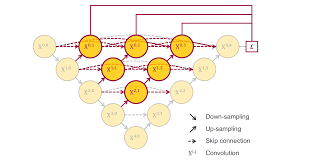

U-Net++

Paper: 《UNet++: Redesigning Skip Connections to Exploit Multiscale Features in Image Segmentation》

Accepted by TMI 2019.

文章解读:https://zhuanlan.zhihu.com/p/44958351

U-Net++ 的第一个优势就是精度的提升,通过整合不同层次的特征加强信息交互;第二个是灵活的网络结构配合深监督,让参数量巨大的深度网络在可接受的精度范围内大幅度的缩减参数量。